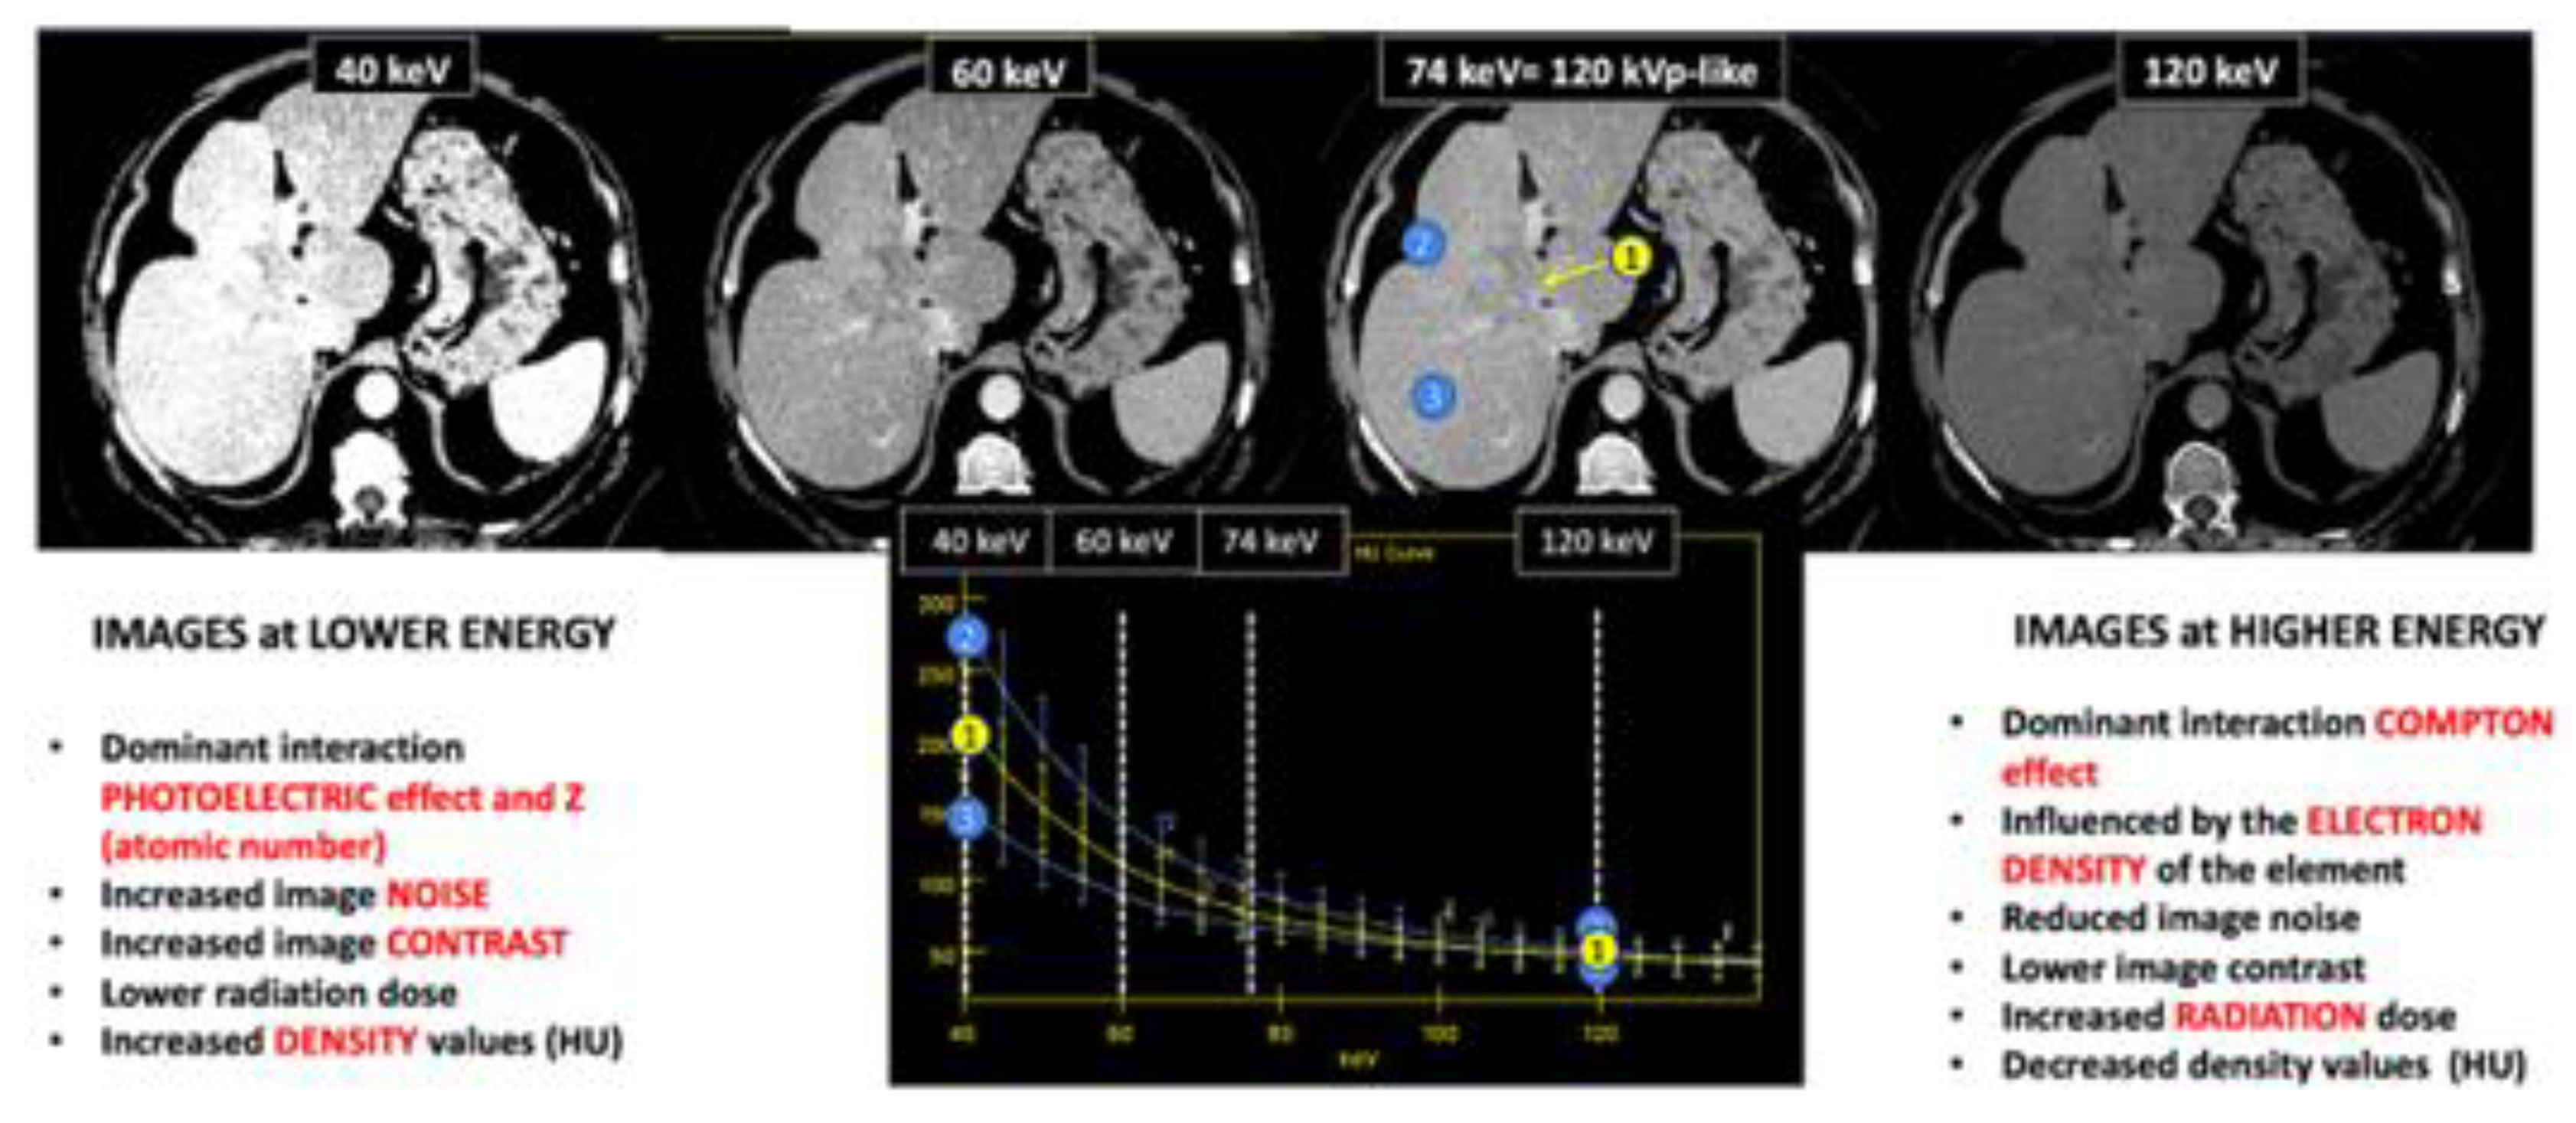

2.2.2. Energy-Selective Images